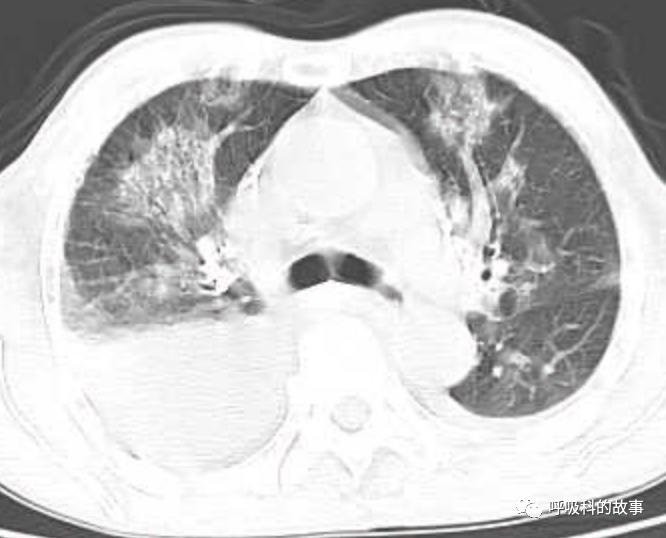

接着,我打开电脑看病历:患者,男,68岁,主诉:发热、头痛伴乏力10余天,咳嗽4天。肺部CT一看是右下叶大片实变肺炎,双侧少量胸腔积液,两上肺内中带片絮状斑片状影。2020.11.30 在外院检查 PCT 7.42ng/ml,ALT 199U/L,AST 250U/L,白蛋白24.7g/L,CRP 108.7mg/L,乳酸脱氢酶LDH388U/L(正常50-240),钾3.27mmol/L;血常规:白细胞4.9*10^9/L,中性85.2%。在外院给予了亚胺培南2天和本院美罗培南治疗2天后,效果并不理想。

(6)肺部影像以大叶性肺炎为主,其他部分是合并肺水肿的影像;